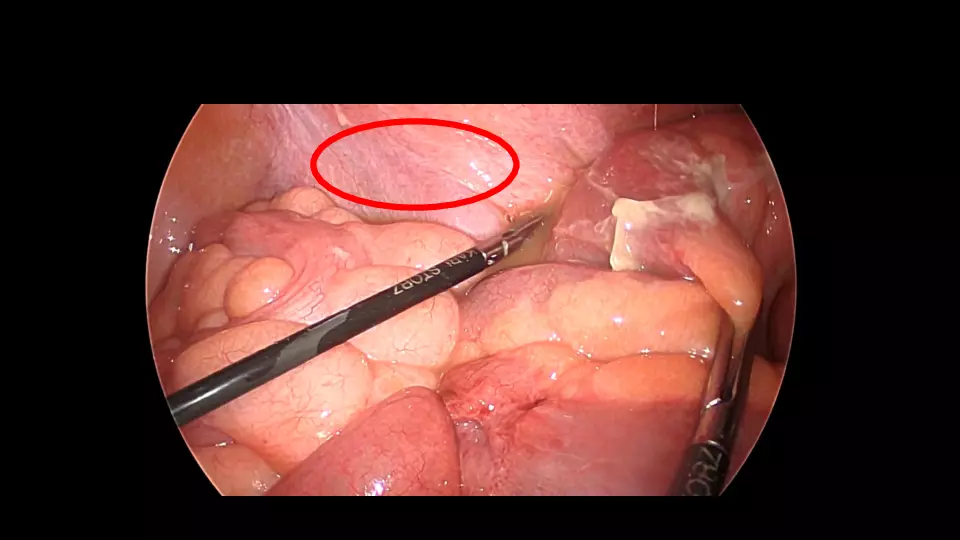

「反跳痛があります」と記載された紹介患者や、研修医からコンサルトにおいて、意外と腹膜炎ではないパターンが散見されます。 若手外科医だからこそ語れる腹膜炎のはなしを聞いてください。 #腹膜炎,#反跳痛の診かた,#コンサルト,